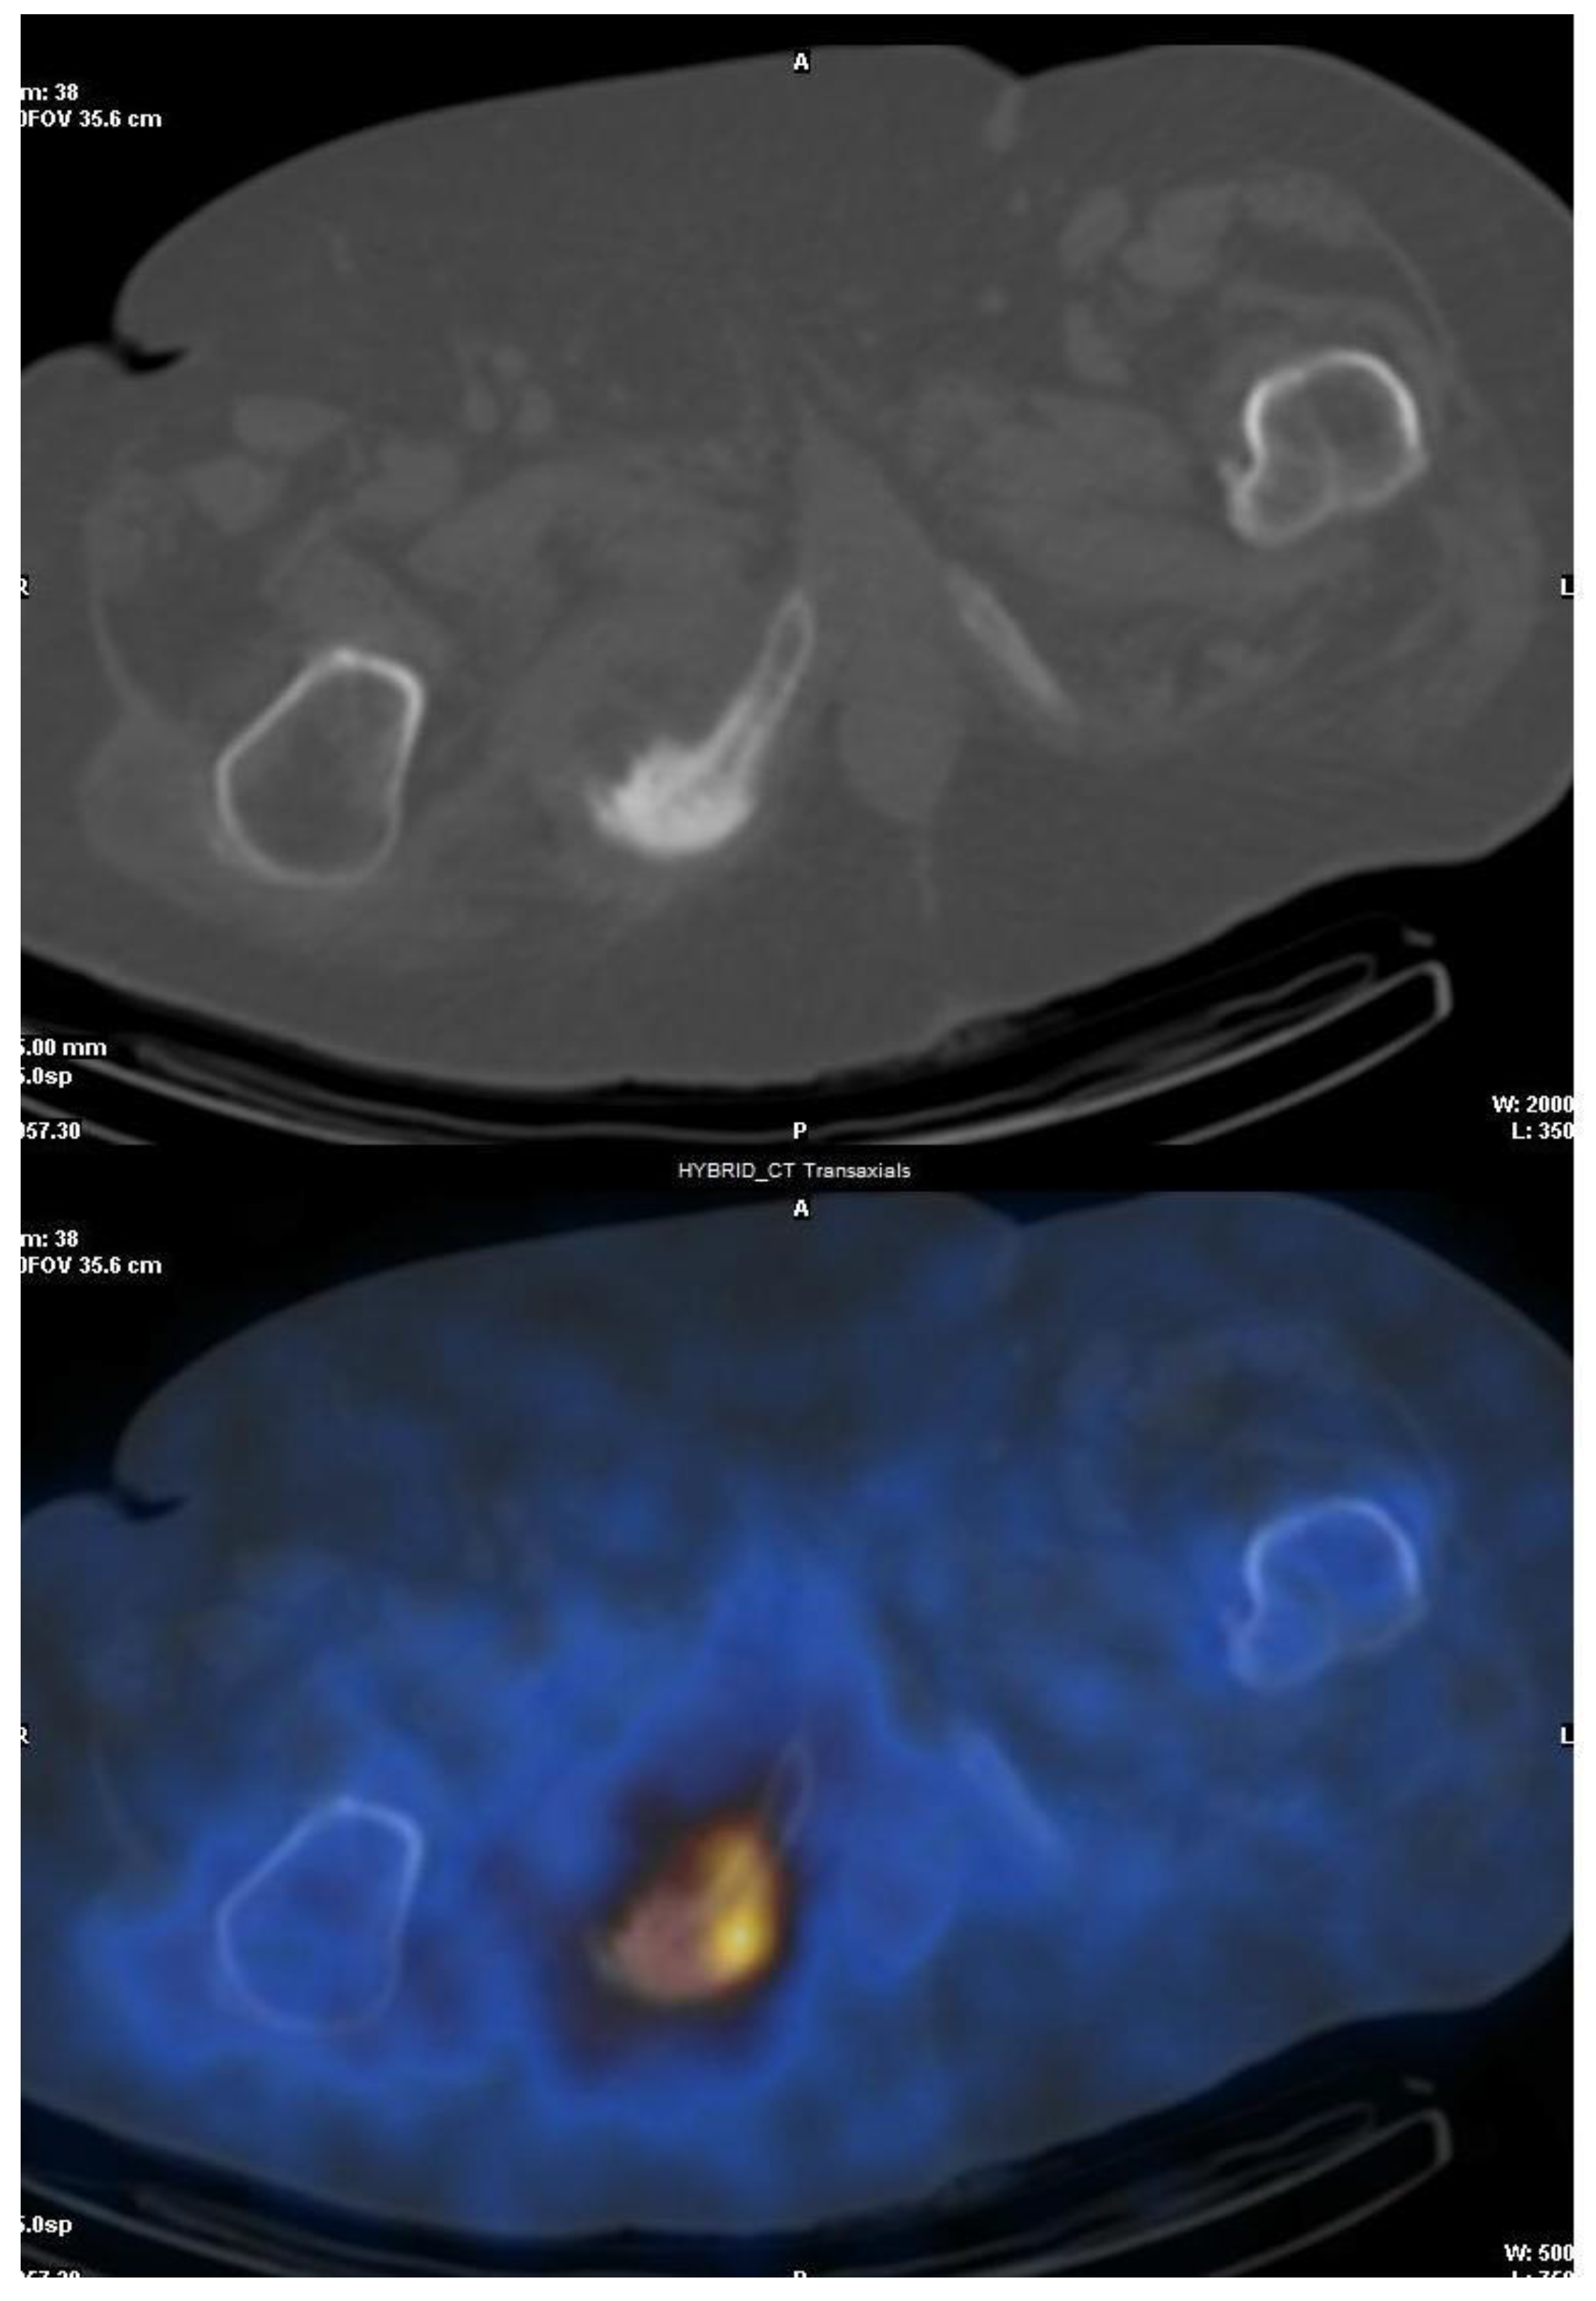

3.2. Fluorine-18-Fluorodeoxyglucose (18F-FDG) with Positron Emission Tomography (PET/CT)